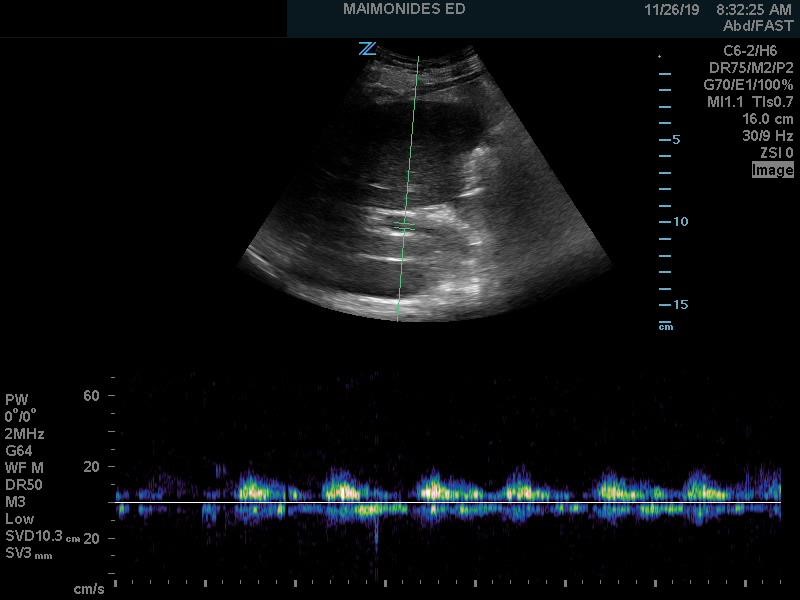

Once a view is obtained, a pulsed wave doppler should be placed within the hepatic vein, attempting to position at an angle parallel to the flow of the vessel for optimal waveform (Figure 2).

Figure 2. Normal hepatic vein Doppler (S>D wave)7

a= atrial kick

S= atrial systolic filling

D= atrial diastolic filling

The venous flow within the hepatic veins can be best thought of as a central venous pressure (CVP) tracing from the right atrium, reflecting the cardiac cycle of the right heart. Understanding this, the hepatic venous doppler waveform helps not only in the evaluation of venous congestion but also right heart function. The typical CVP tracing reveals an atrial kick, followed by systolic and diastolic filling of the atrium. A normal hepatic venous doppler will reveal a retrograde “a” wave followed by two antegrade “S” and “D” waves, as seen in Figure 2. A normal waveform consists of a relatively small a wave with the S wave larger than the following D wave (S>D), as a there is greater primary venous flow into the atrium during systole. As the venous system becomes engorged, the S wave becomes smaller relative to the D wave (S<D), due to a physiologic change from primarily systolic filling to a relative increase in passive diastolic filling of the heart (Figure 6A). As congestion continues, there is S wave reversal as seen in Figure 6B. The relative doppler flows noted in these tracings can thus help determine whether the heart is providing sufficient forward flow to prevent further venous engorgement, as well as help in the identification of right heart lesions, such as tricuspid regurgitant flows. Regurgitant flows may affect the pressures that are placed on the venous system. As such, hepatic vein flows can provide critical information about how the heart functions in response to increased venous congestion and determine when we have strained the heart to a point where it may benefit from de-resuscitation.